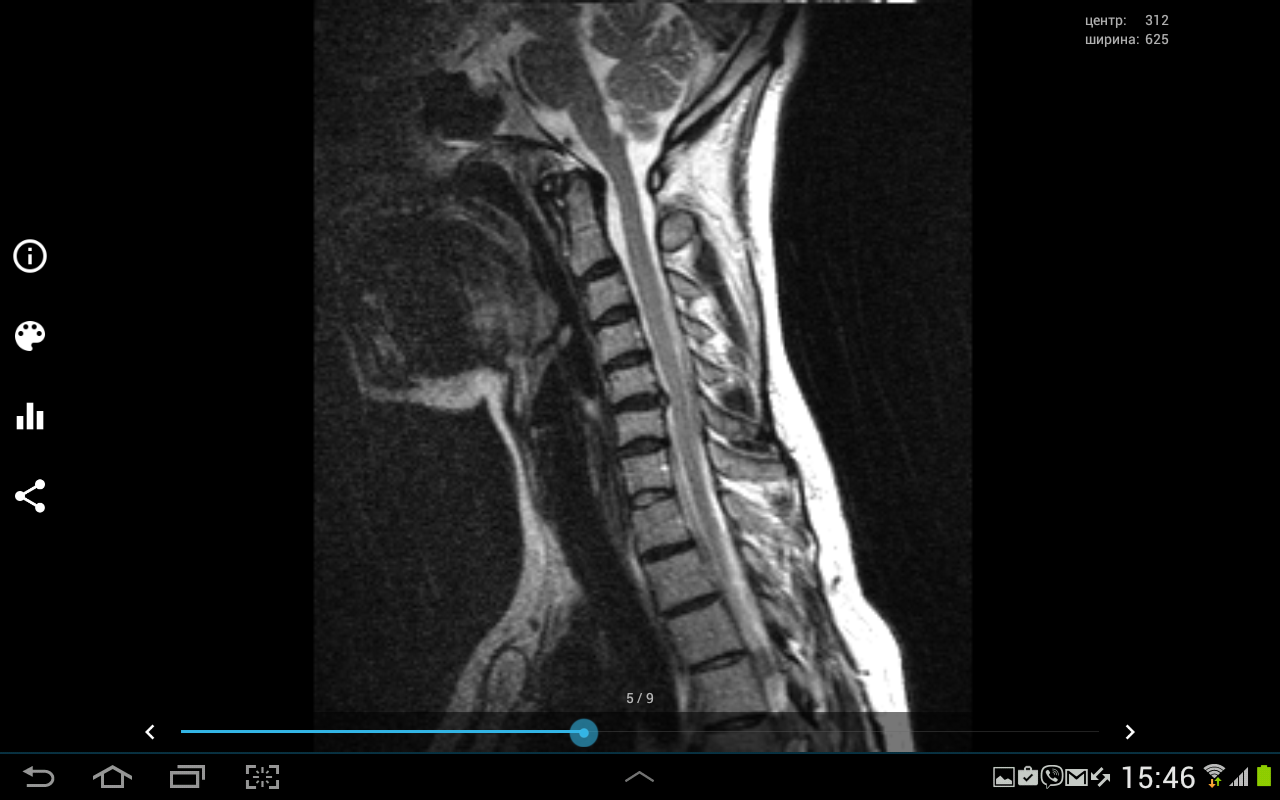

Здравствуйте подскажите пожалуйста надо делать операцию или нет? Наш нейрохирург говорит что надо, невролог говорит что не надо не знаю кого слушать, помогите. У меня ноющие боли в шее, переходящие на левую руку и под лопатку,иногда немеют кончики пальцев на руках, также есть иногда головные боли!?

- МРТ